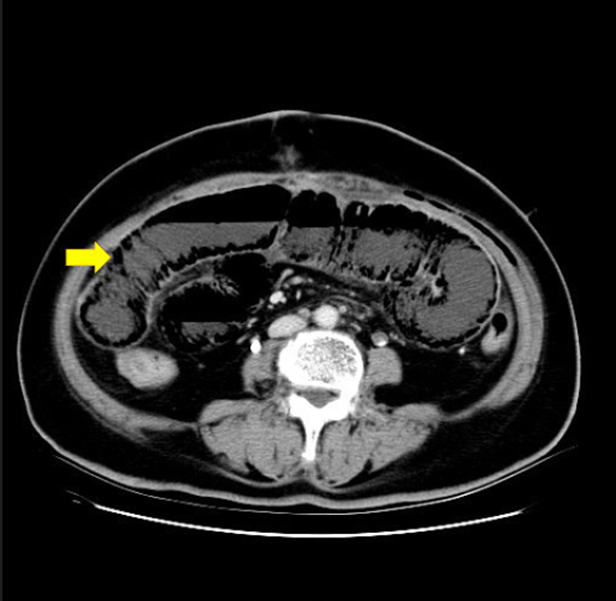

A female aged 48 years underwent neoadjuvant radiotherapy for the rectal adenocarcinoma preoperatively and low anterior resection for the tumor one month afterward after complete radiotherapy. Because of the very low colonic anastomosis and the previous radiotherapy, the ileostomy coincided for fecal diversion. Primarily, her postoperative recovery was smooth. After her oral intake without any discomfort, she was discharged after post-op day 7. Withal, she returned to our hospital due to persistent vomiting, progressive abdominal pain and abdominal bloating after she discharged 2 days afterwards. Physical examination averred abdominal bloating and hypoactive bowel sound but no peritoneal sign. Notwithstanding the severely edematous ileostomy, no gangrene change existed; sepsis, leukocytosis (WBC: 19400/mL), metabolic acidosis, and elevated lactate levels (7.5 mmole/L) were evinced. The abdominal computed tomography (CT) from the stomach to the small bowel denoted diffuse dilatation (Figure 1) and pneumatosis intestinalis (PI) and portal venous gas (PVG) (Figure 2, 3). Owing to these symptoms, she was admitted in our intensive care unit for advance treatment. Non-operative treatment because there was no peritoneal sign and the ileostomy was still in good appearance. Those treatments covering nasogastric tube (NG) for gastrointestinal (GI) tract decompression, large amount fluid supply (3000ml/day) and antibiotics (ceftriaxone 1gm Q12H and metronidazole 500mg Q8H) was for her sepsis status. Her abdomen and ileostomy conditions scrutinized could be contributed to emergent operations if getting worse. The edematous ileostomy started to improve two days subsequently. The ileostomy-made flatus and stool passage were on readmission day 5. The oral liquid diet ingestion began; the transfer to the general ward was on re-admission day 7. Attributed to no abnormal abdominal lesion, the soft diet was applied. Eventually, she was discharged on re-admission day 12. Till present, no other abdominal lesion was identified in out-patient department follow up.

Figure 2: Dilated bowel with intra-mural gas (arrow)